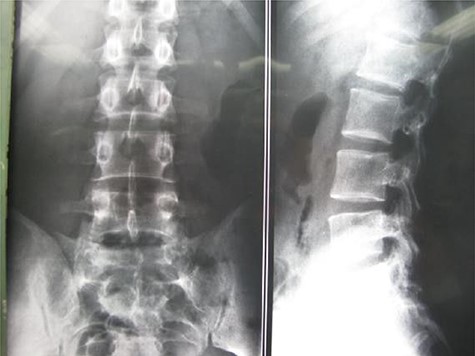

A 24-year-old male presented with acute low back pain with no prior traumatic events. Physical examination was unremarkable except for tenderness over the lower thoracic spine. The laboratory tests including complete blood count, renal function tests, alkaline phosphatase, aspartate aminotransferase, alanine aminotransferase, serum calcium, serum phosphorus and parathyroid hormone were all within normal limits. Initially, the patient was treated conservatively but the pain did not improve. Lumbar X-ray showed mild height loss and fracture of the superior endplate of T12 vertebra (Fig. 1). Computed tomography (CT) showed a multi-lobulated osteolytic lesion within the T12 body with extension to the right pedicle and transverse process (Fig. 2). Magnetic resonance imaging (MRI) revealed a well-defined lesion with low signal intensity on T1 and high signal intensity on T2 weighted images (Fig. 3). The bone scan showed a cold spot at the site of the lesion. The patient underwent surgery and excisional biopsy through the posterior approach. A large clear fluid-filled cavity was curetted and the cavity was filled with an autologous bone graft from iliac crest. Posterior spinal fusion was performed with instrumentation with pedicle screws from T10 to L2 and a mixture of autologous bone graft and allograft was used to achieve better fusion (Fig. 4). Pathology report confirmed the diagnosis of SBC and the patient received no further treatment (Fig. 5). The patient had no recurrence in 10-year follow up.

Case 1, (A): Anterior–posterior; (B): Lateral pre-operative X-ray.